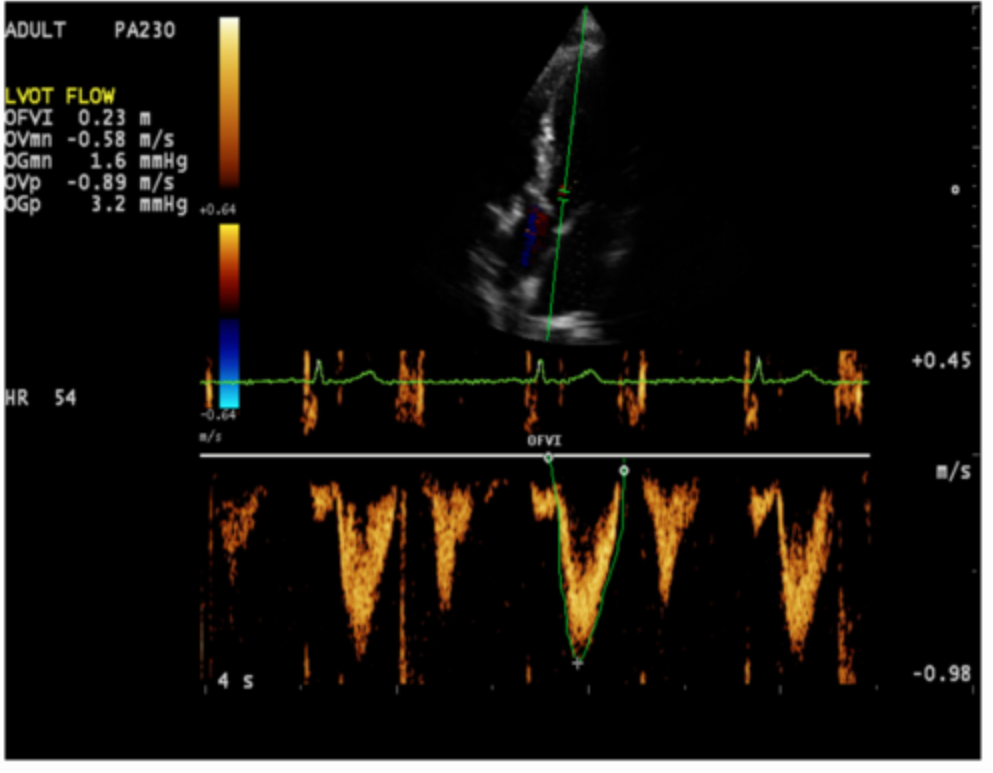

What is being measured on the Doppler tracing?

a. resistive index

b. peak diastolic velocity

c. peak systolic velocity

d. end diastolic velocity

peak systolic velocity

Use your cursor to measure the end diastolic velocity of the third waveform. Use your mouse to position the cursor and click to set your answer.

(green)